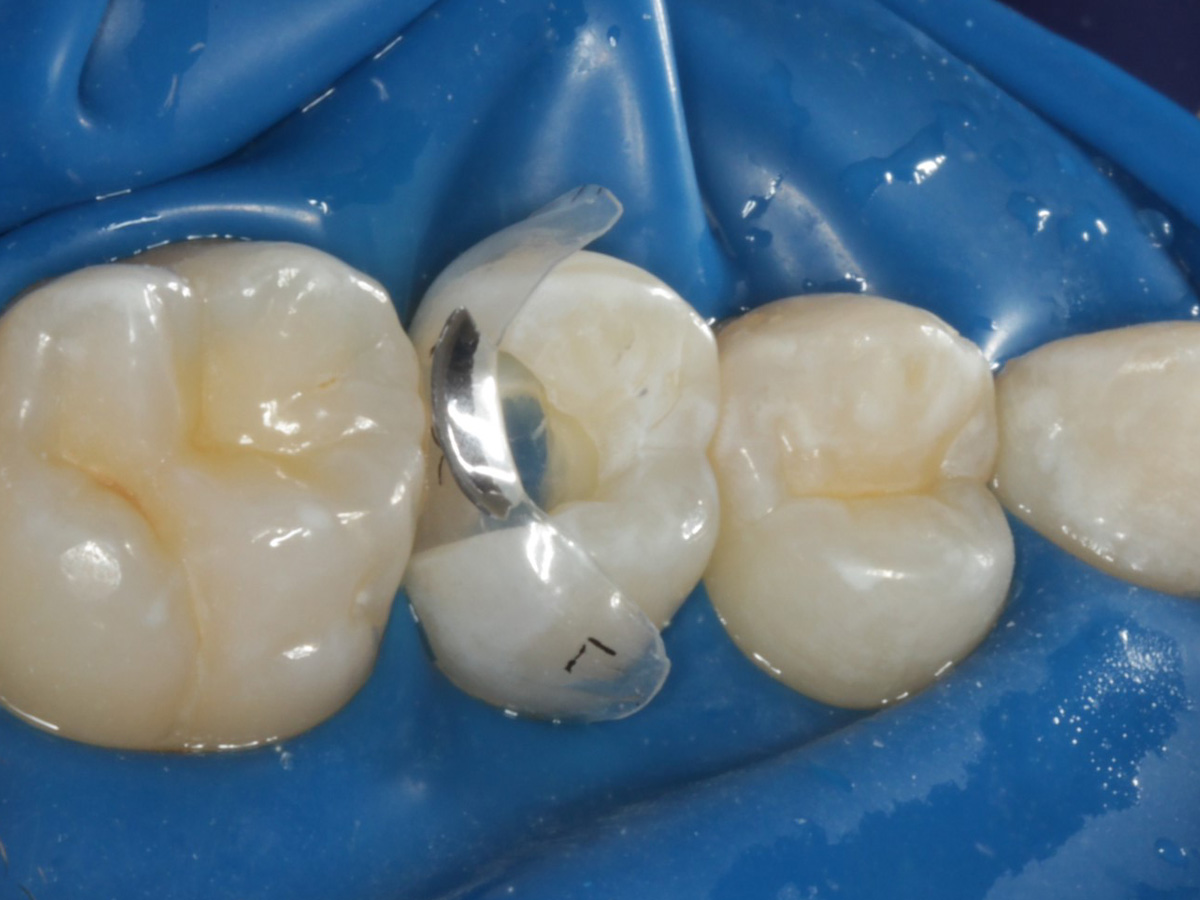

Abbildung 13

Abbildung 14

Nach Anbringung des Bioclear Twin Ring Universal und Lichthärtung des Einkomponentenadhäsivs

Starke Separation der Zähne durch hohe Spannkraft des Twinrings für strammen Kontaktpunkt

Bewusst kein Keil zur Vermeidung unerwünschter Matrizenverdrückung